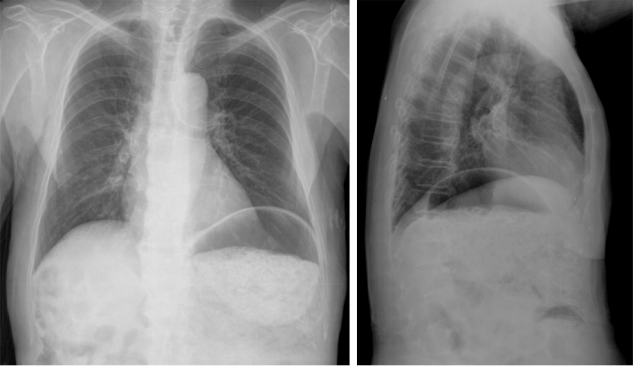

rx

Rx de Tórax 2P: llama la atención la cámara gástrica dilatada con abundante contenido con nivel hidroaéreo.

Se observa un patrón en «miga de pan» que correlacionándolo con la radiografía corresponde con contenido en el interior del estómago dilatado.